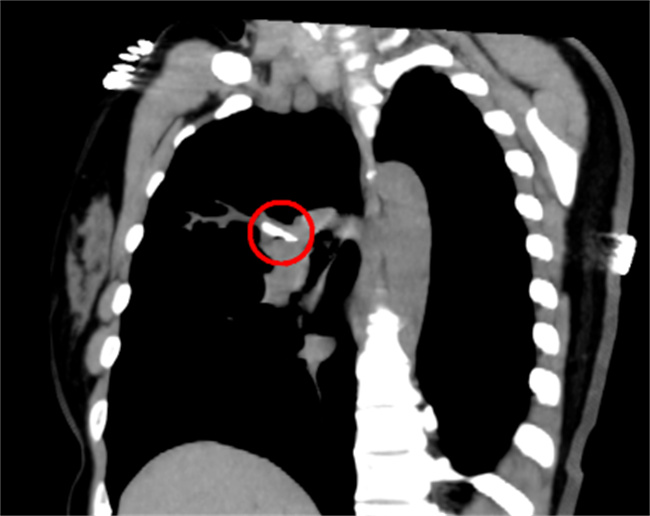

如果只是单纯性刺激性干咳,不需要拍CT。有肺炎的情况下还会有胸闷以及气急的症状,绝大部分都是上呼吸道感染会有一种异物感。如果没有这类的情况,就无需过于的担心,是气道修复的一个过程。

在患有新冠之后,如果没有任何的症状,这就被称之为无症状。有症状的主要就是发热,咽喉疼痛咳嗽等等。根据症状的轻重也可以分成多种,一般症状全部都是在上呼吸道,比如咽喉疼痛,发热咳嗽,流鼻涕,鼻塞,但没有出现肺部影像学的变化。

可如果有上呼吸道症状的同时还出现肺炎的表现,这就说明是普通型。如果氧饱和度明显低于93,有明显的胸闷等症状,这就属于一种危重型。